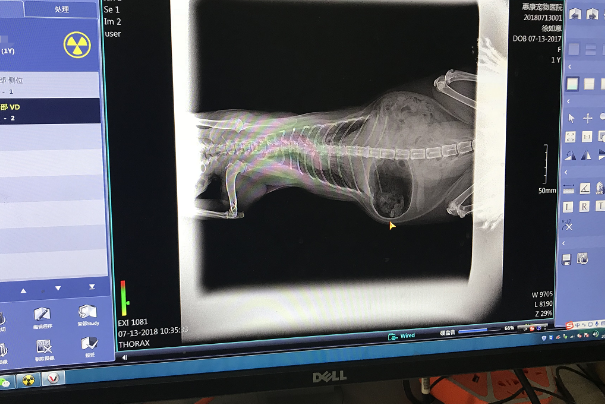

宠物拍片的价格因地区、宠物类型、病情不同而有所差异。一般而言,在城市大型宠物医院进行X射线检查的费用比较高,平均在200元至500元左右,而在小型宠物诊所或社区诊所等医院相对便宜,价格在100元至300元左右。

需要注意的是,部分疑难复杂的病情需要进行CT或MRI等检查,费用可能更高。而且,价格不仅仅只受地区、宠物类型、病情等因素的影响,也与各医院自身的服务水平和设备条件有关。